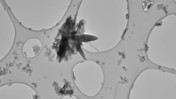

Gıda ve su yoluyla bulaşan "vibrio" bakterisinin neden olduğu kolera, ishale ve dolayısıyla vücutta su kaybına yol açıyor. Hastalık, tedavi edilmediği takdirde ölümcül olabiliyor.